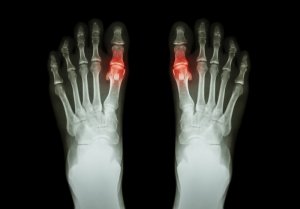

Gikt er en sykdom som forårsakes av at mikrokrystaller av urinsyre opphoper seg i leddene. Disse krystallene buler ut under huden eller de avleirer seg i urinrøret.

- Til å begynne med, kan et eller flere ledd bli angrepet. Det er som oftest stortærne, knærne eller anklene. Dette angrepet kan forsvinne i løpet av et par dager men kan komme tilbake innimellom.

- Vanligvis er leddene som er angrepet varme og røde (betente). Oftest er de også veldig følsomme og hovne.